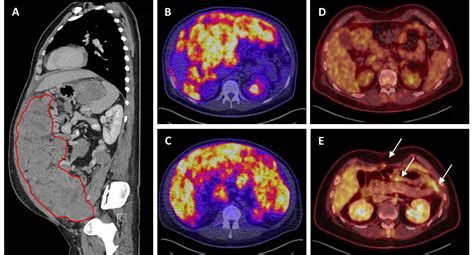

Imaging studies such as computed tomography (CT) scans, magnetic resonance imaging (MRI), and positron emission tomography (PET) scans are often used to visualize the tumor and assess its extent. These imaging techniques can help identify the location and size of the tumor, as well as any metastases.